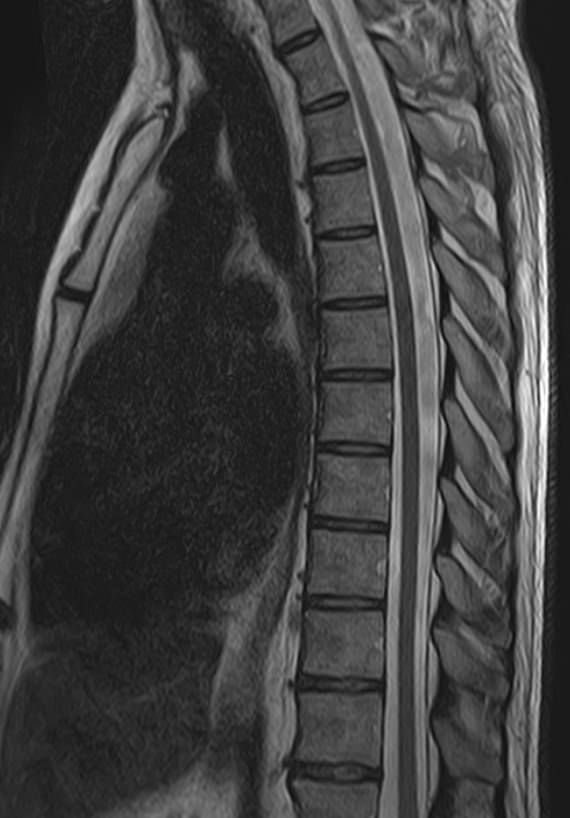

Магнитно-резонансная томография является современным, высокоинформативным и доступным методом обследования позвоночника. МРТ позволяет оценить состояние костных структур позвонков, спинного мозга, нервных корешков и окружающих мягких тканей.

В клинике «Доступная медицина» выполняется МРТ различных отделов позвоночника. В зависимости от уровня поражения можно провести МР томографию шейного отдела, грудного отдела, пояснично-крестцового отдела позвоночника и копчика.